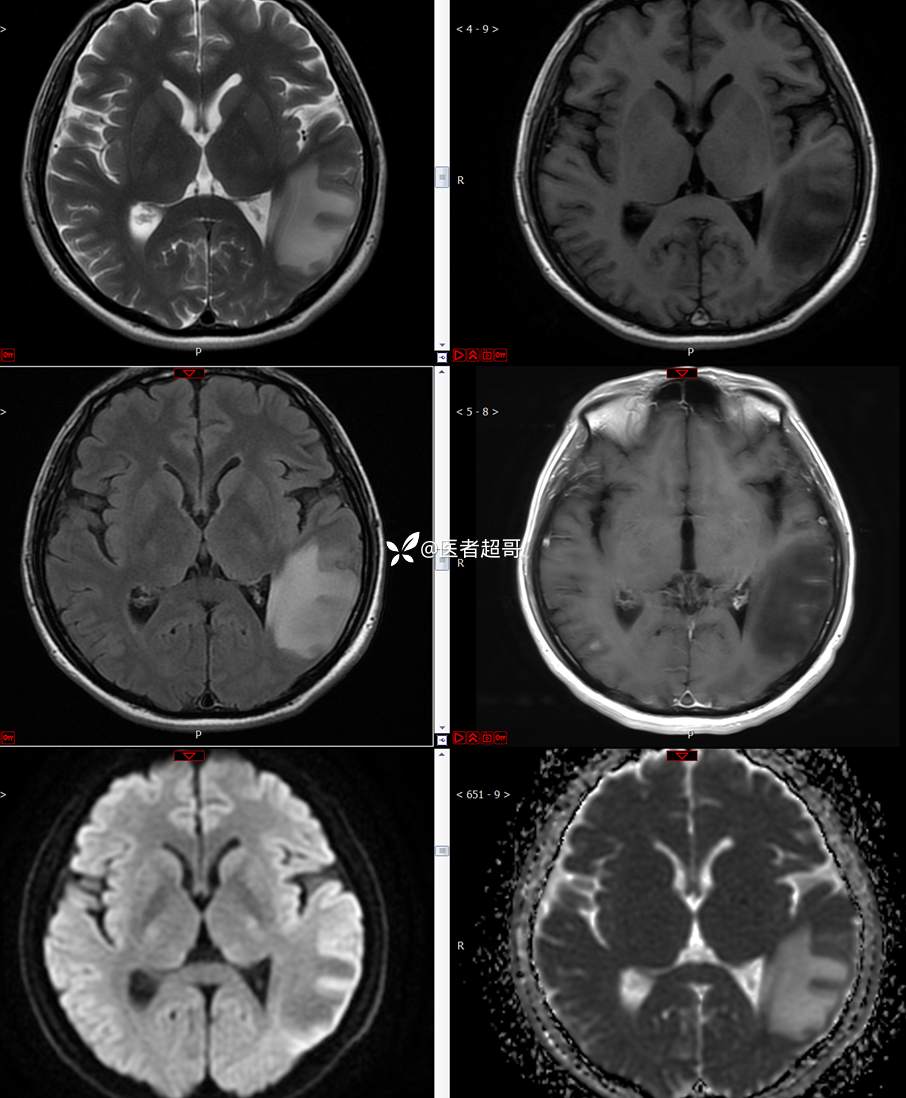

【影诊笔记773】头痛、头晕10天,CT、MRI齐全,请高诊!

主 诉:头痛、头晕10天

现病史:患者10天前无明显诱因感头痛、头晕,伴记忆力减退,无恶心、呕吐,无肢体抽搐及肢体活动不灵等,于我院就诊,行颅脑MR示颅内多发占位,现患者为求进一步治疗于我院就诊,以“颅内占位”收入我科。患者目前神志清,精神可,饮食、睡眠正常,体重无明显变化。

既往史:既往急性肝功能衰竭病史.